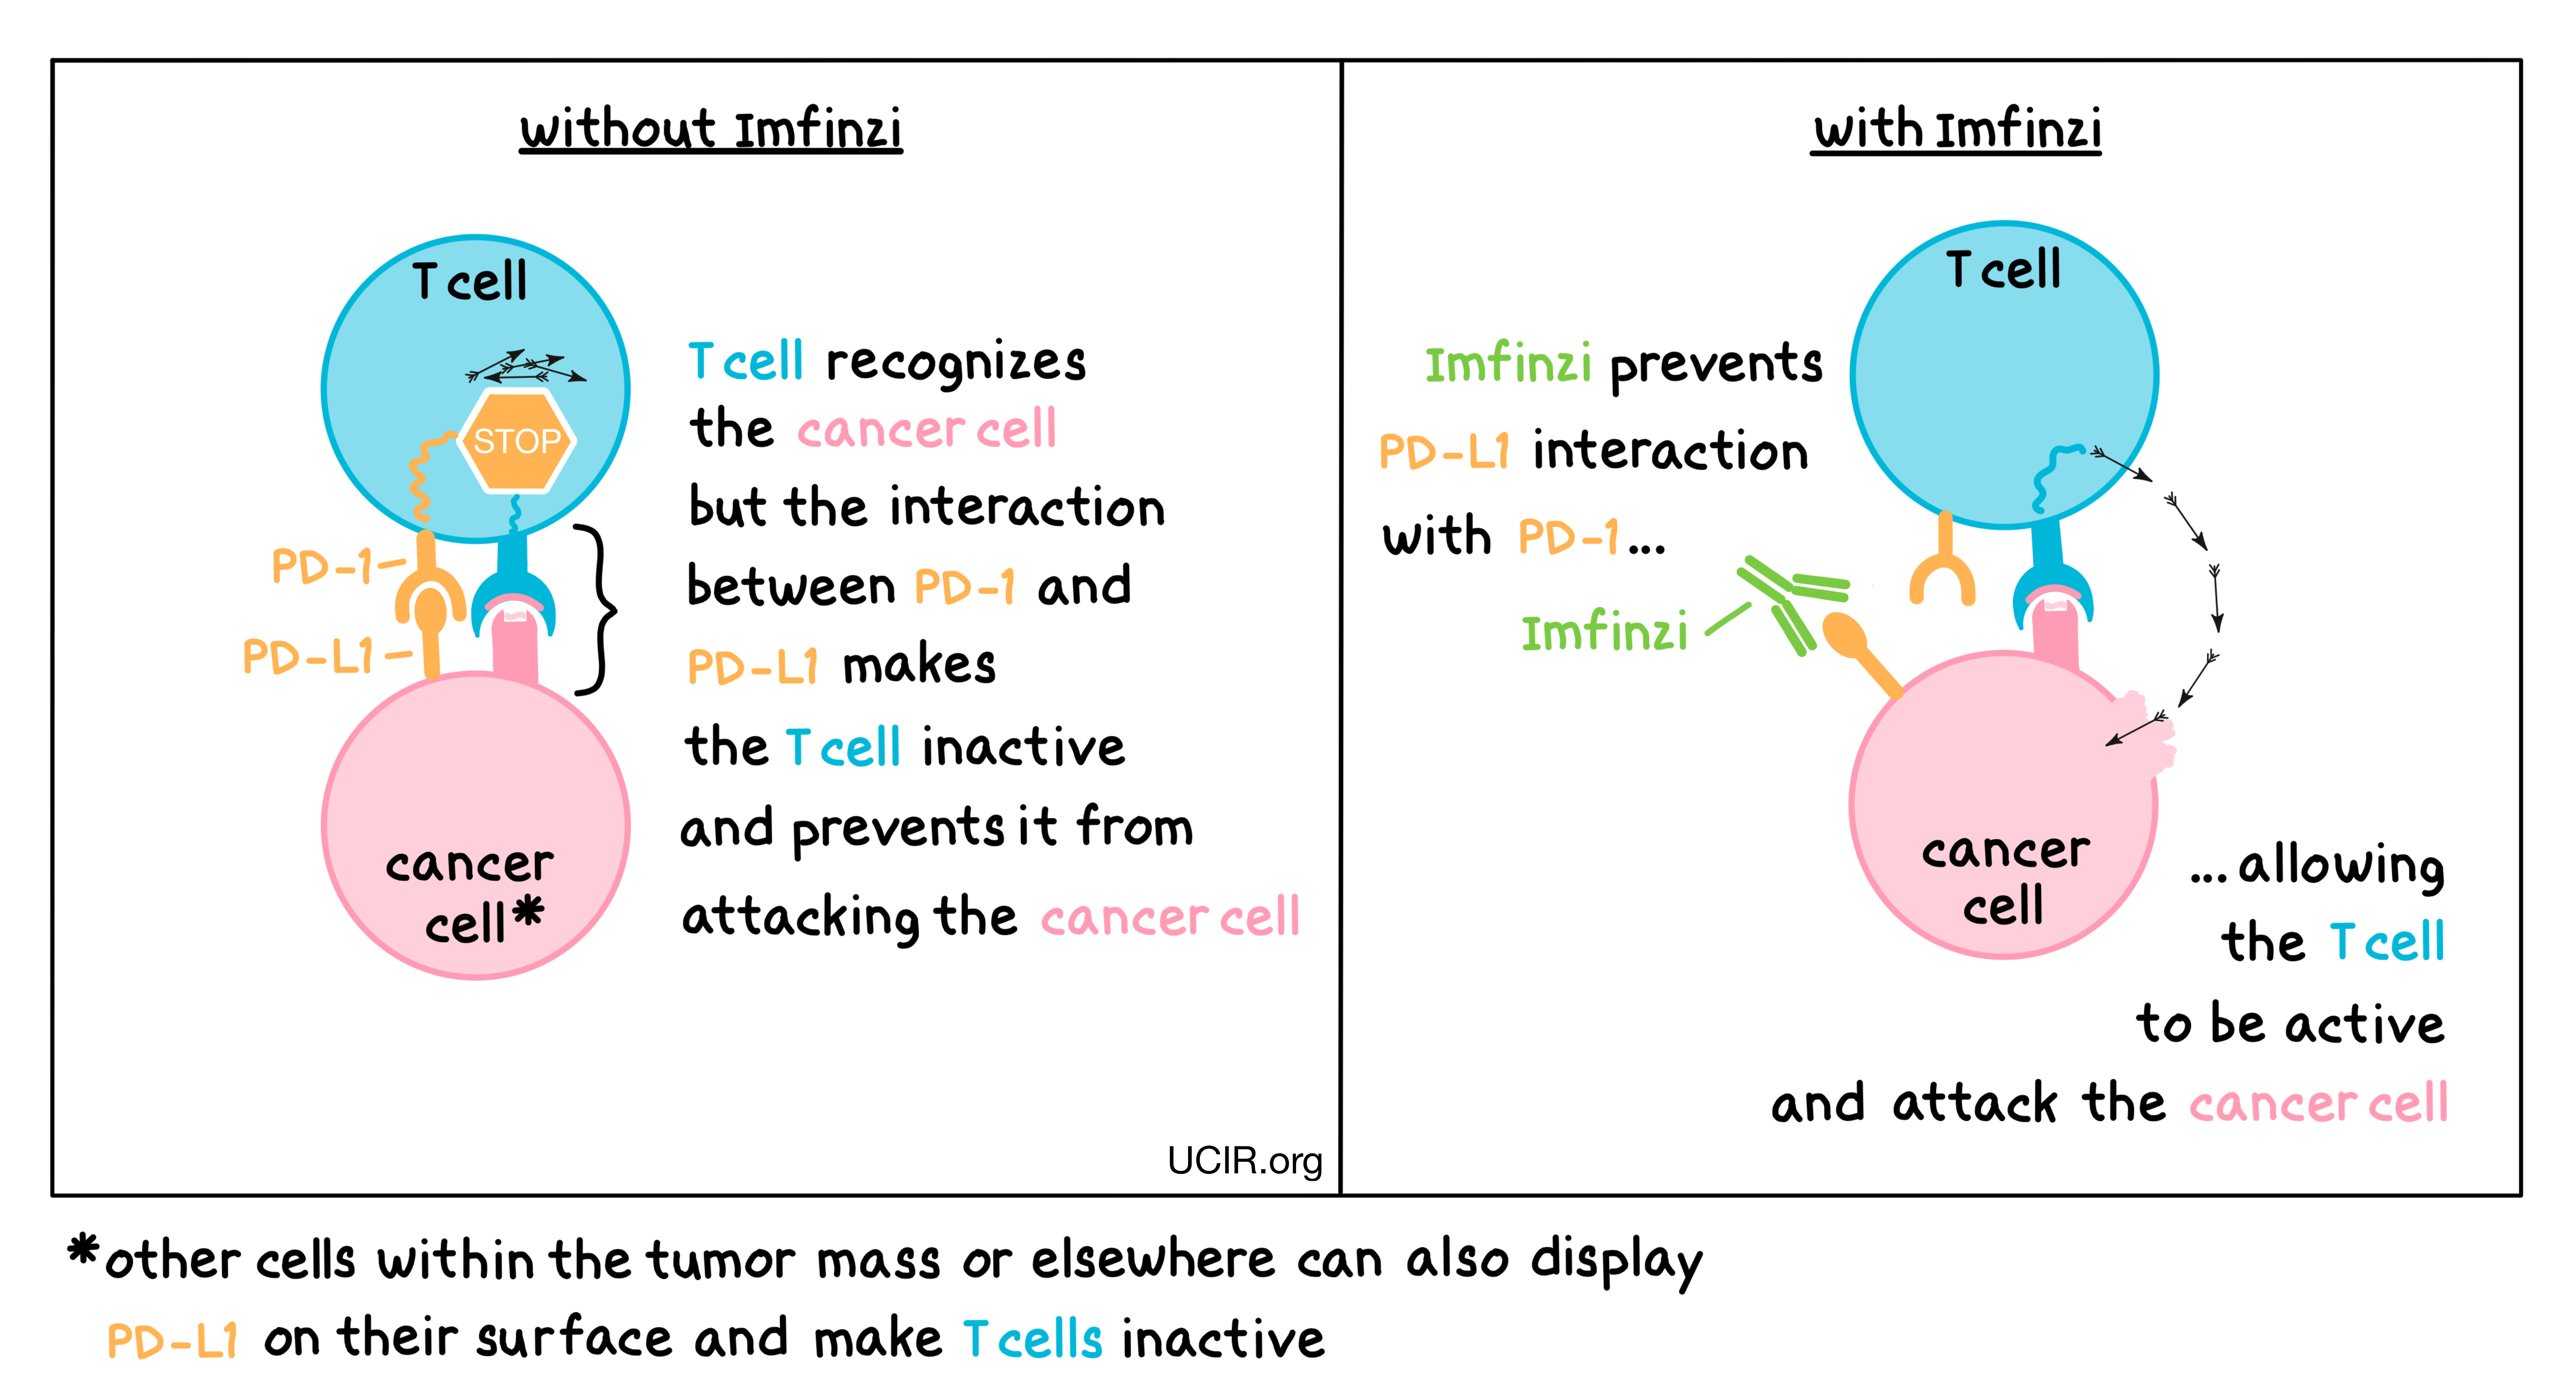

查看详情 Durvalumab 疗法获胃癌/GEJ 癌优先审评

Durvalumab 疗法获胃癌/GEJ 癌优先审评

美国食品药品监督管理局 (FDA) 已对 durvalumab 用于治疗可切除、早期和局部晚期 (II-IVA 期) 胃癌和胃食管连接部 (GEJ) 癌...